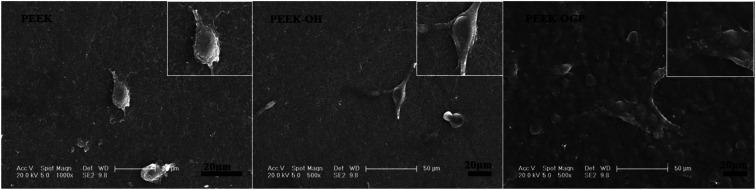

Polyetheretherketone (PEEK), as the most promising implant material for orthopedics and dental applications, has bone-like stiffness, excellent fatigue resistance, X-ray transparency, and near absence of immune toxicity. However, due to biological inertness, its bone conduction and bone ingrowth performance is limited. The surface modification of PEEK is an option to overcome these shortcomings and retain most of its favorable properties, especially when excellent osseointegration is desired. In this study, a simple reaction procedure was employed to bind the osteogenic growth peptide (OGP) on the surface of PEEK materials by covalent chemical grafting to construct a bioactive interface. The PEEK surface was activated by ,'-disuccinimidyl carbonate (DSC) after hydroxylation, and then OGP was covalently grafted with amino groups. The functionalized surface of PEEK samples were characterized by X-ray photoelectron spectroscopy (XPS), Fourier-transform infrared spectroscopy (FT-IR), water contact angle measurement and biological evaluation . OGP-functionalized PEEK surface significantly promoted the attachment, proliferation, alkaline phosphatase (ALP) activity and mineralization of pre-osteoblast cells (MC3T3-E1). The rat tibia implantation model is adopted and micro-CT analyses demonstrated that the OGP coating significantly promoted new bone formation around the samples. The and results reveal that the modification by covalent chemical functionalization with OGP on PEEK surface can augment new bone formation surrounding implants compared to bare PEEK and PEEK implant modified by covalently attached OGP is promising in orthopedic and dental applications.